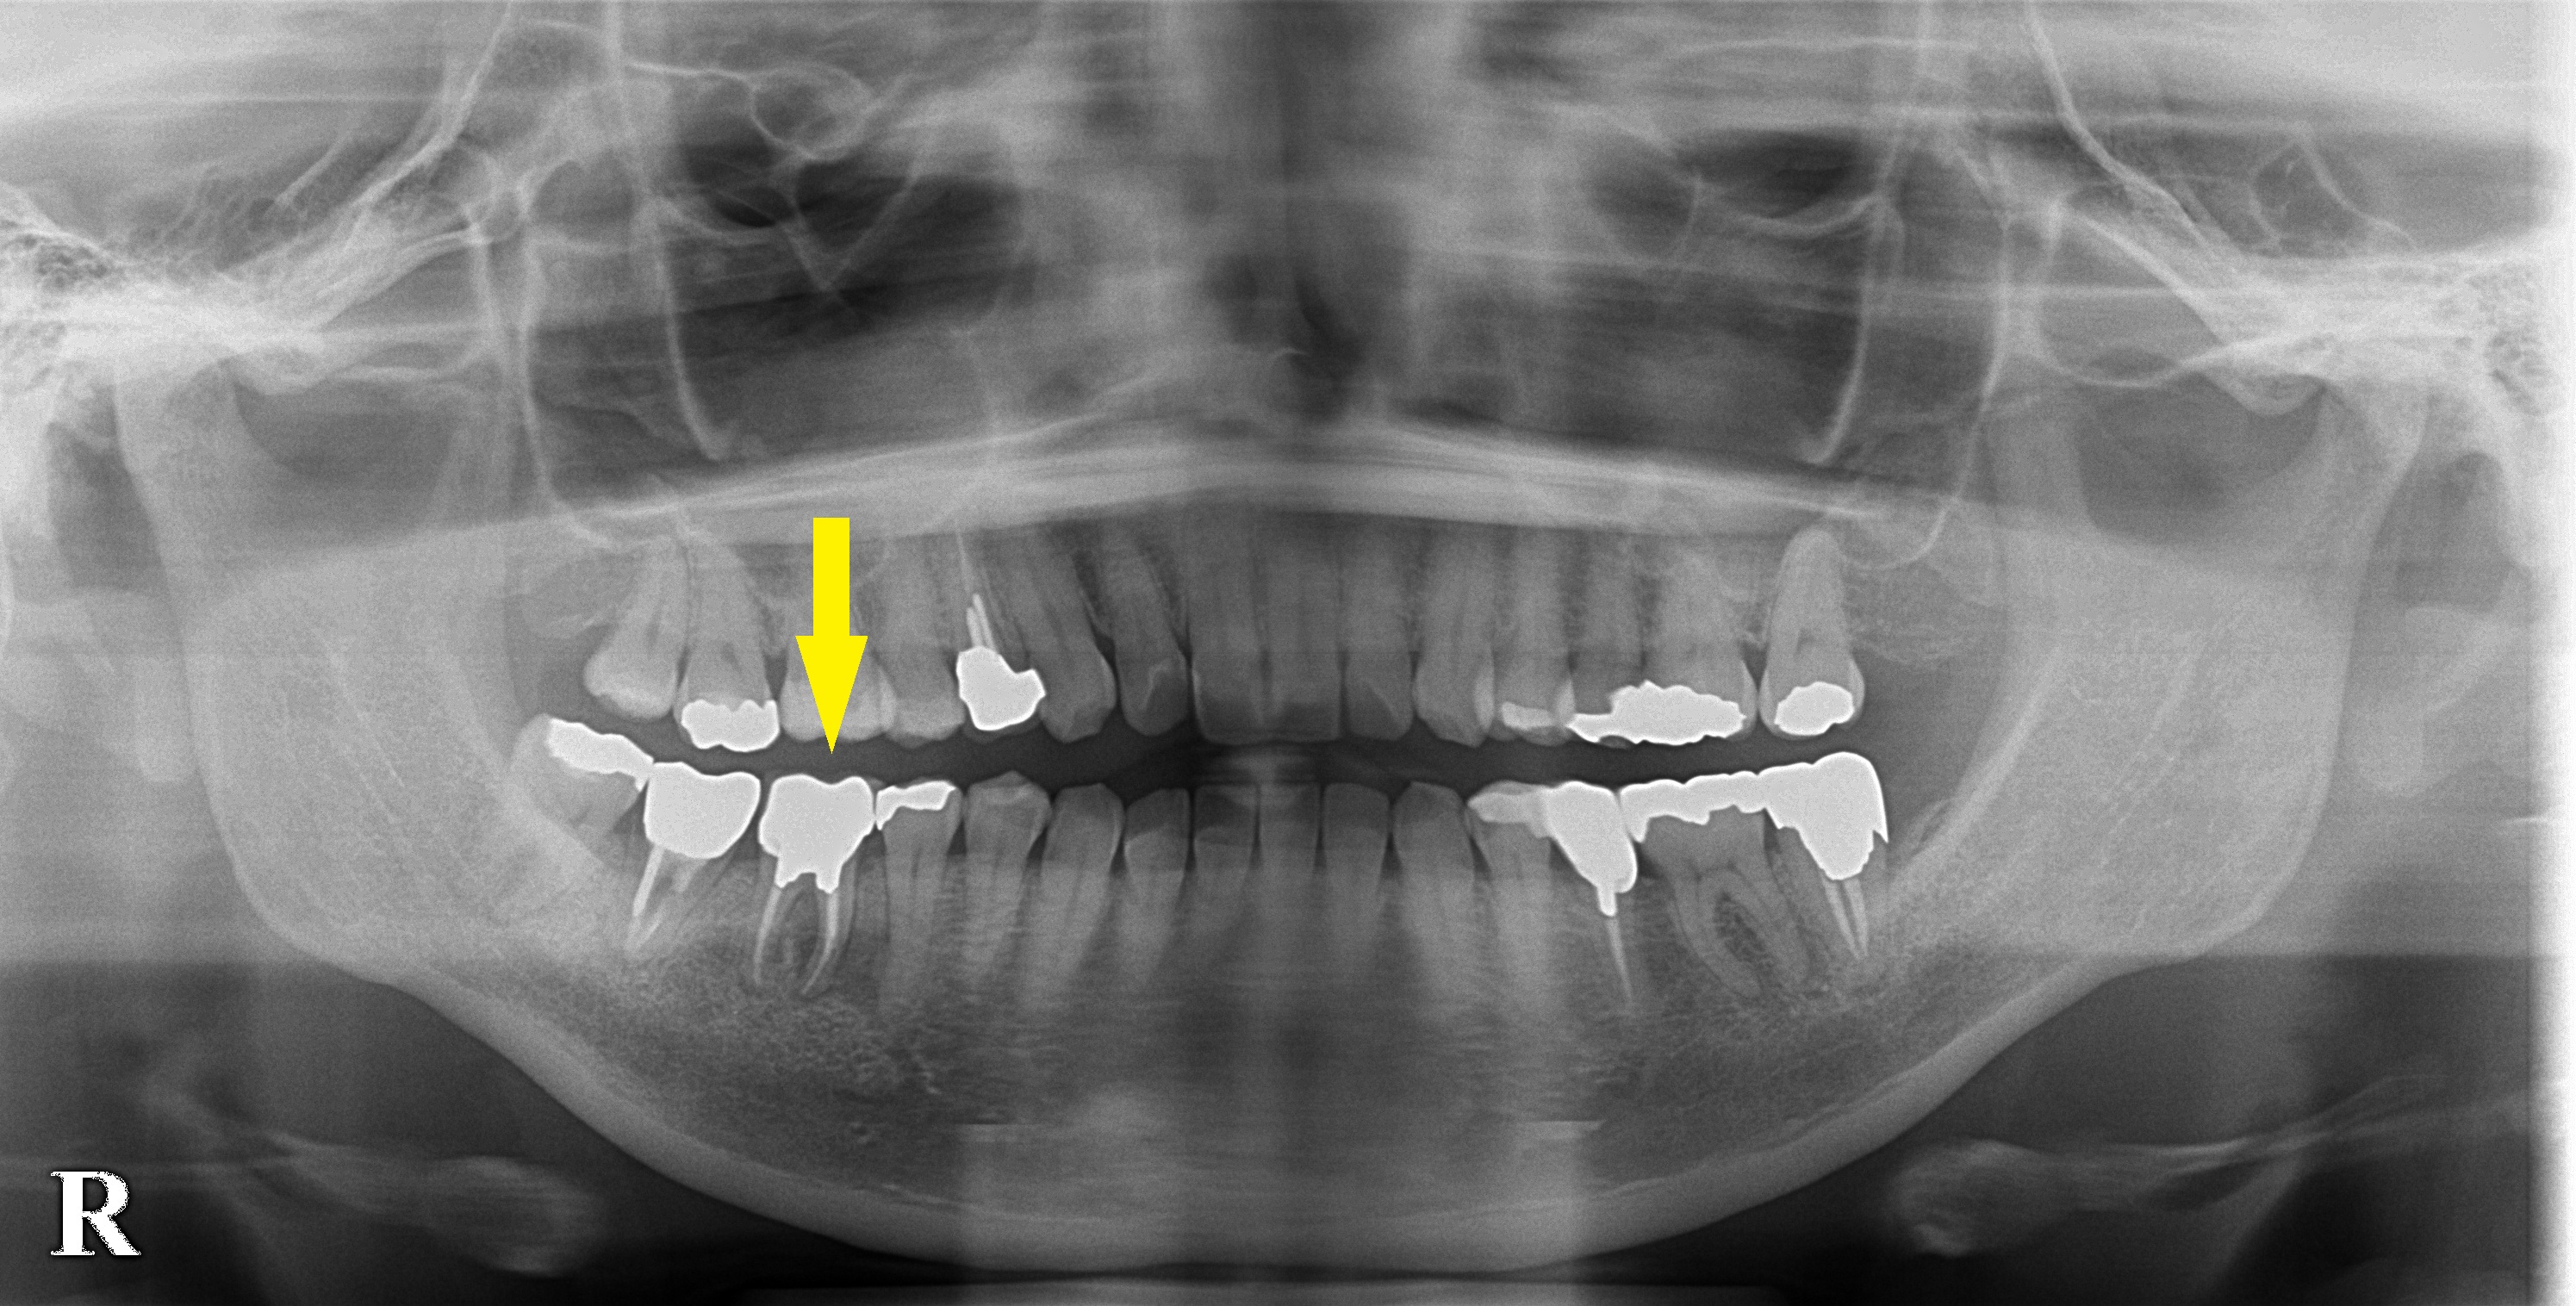

レントゲン写真ではさほどではないのですが、CTを撮影してみると歯根の間、周囲の骨が大きく吸収されてしまっていました。

おそらく、歯根の間の部分に穴が開いてしまっているか、歯根が破折していると考えられました。

やはり、この歯を保存するのは困難であると説明させていただき、抜歯して治癒を待ってインプラントをお勧めしました。